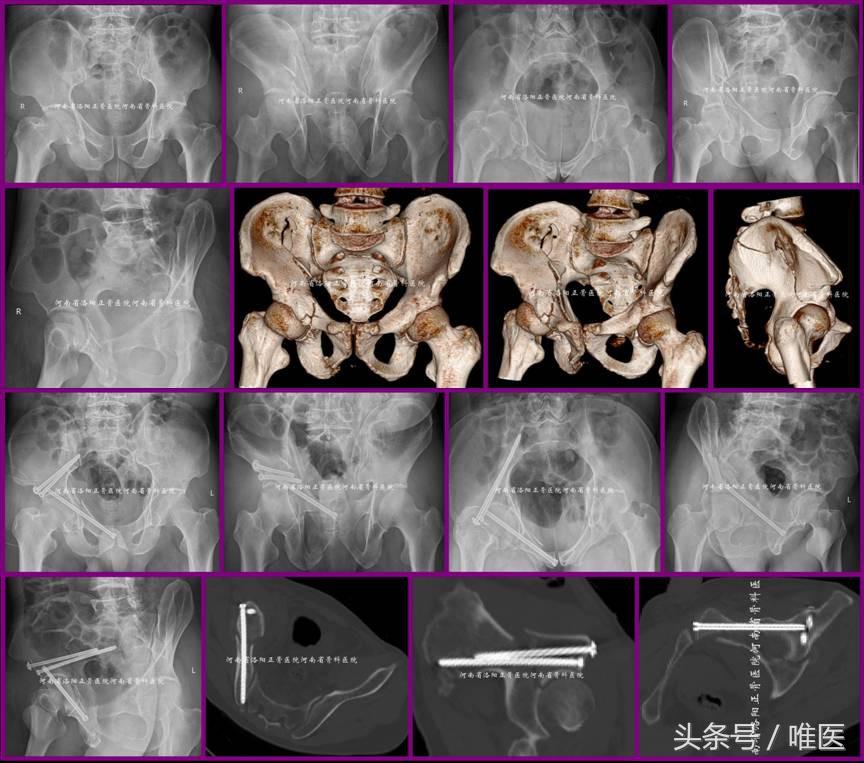

3. 用于治疗髋臼双柱骨折(即OTA-62C)的高位前柱骨折部

病例3:一例31岁男性病人,以高处坠落致右髋部疼痛活动受限两天入院。入院诊断:右侧髋臼骨折(OTA-62C1.2)。经髂腹股沟入路(ilioinguinal approach)显露骨折。先复位双柱骨折的高位前柱骨折部至主体骨并经皮置入两枚LC-II螺钉固定,然后应用Matta钳夹持复位后柱骨折部并经主体骨及复位后的高位前柱应用两枚螺钉固定,最后应用接骨板螺钉固定髋臼前柱的低位骨折部。术前及术后影像资料见图13。

图13. LC-II螺钉用于固定髋臼双柱骨折(即OTA-62C)的高位前柱骨折部。